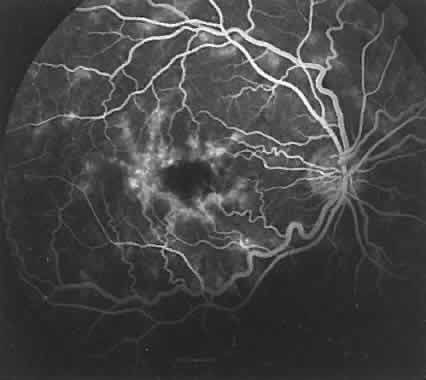

The RPE also functions as an optical barrier because of the presence of pigmented melanosomes (Fig. 6). The density of this pigment varies with retinal location; it is greatest in the foveomacular region and least anterior to the equator. There are more pigmented epithelial cells per unit area in the foveomacular region than in the periphery. Posteriorly, the cells are tall and columnar, with several layers of melanosomes crowded together. Anteriorly, the cells gradually become flatter and more cuboidal, with a corresponding loss of relative pigment concentration (Fig. 7). In any normal eye, regardless of the comparative fundus color, the greater pigmentation in the foveomacular area gives this zone a darker clinical appearance when compared with the remainder of the posterior pole and periphery.

Fig. 7. Relative difference in morphology of RPE. Assuming that each RPE cell has approximately the same number of melanosomes, then the pigment density is a function of height and width of the cells. The RPE in the foveomacular area are tall and columnar shaped in contrast to the more cuboidal RPE cells in the surrounding posterior pole. The greater density of pigment in the columnar cells helps to explain the foveomacular dark spot seen in this normal fluorescein angiograph.